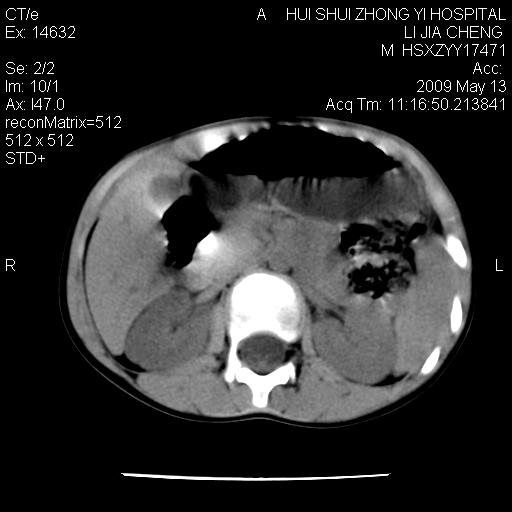

标题: PED1887:男性,6岁。反复脐周疼痛2年余。请各位老师看下腹 [打印本页]

标题: PED1887:男性,6岁。反复脐周疼痛2年余。请各位老师看下腹

该患者可自行好转,大小便未见异常,化验:便未见虫卵,血常规:wbc:8000;淋巴3600,中性45%

脂肪肉瘤可能性大,大血管边界不清,特别是腔静脉。不除外其他腹膜后肿瘤。

是不是有蛔虫哦,楼主图示块影前方肠管壁显著增厚,不除外慢性肠炎或肠壁占位,建议肠道准备后复查

来源于十二指肠水平部病变?建议行进一步检查。

肠管管壁均匀增厚,炎性可能